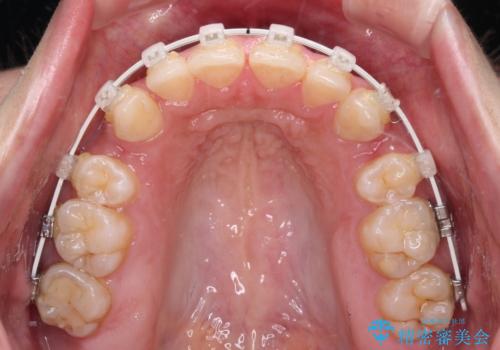

- 矯正装置

- 審美装置

- 治療計画

- 口元の突出感と上下前歯のズレを気にして来院された患者様です。

舌の突出癖により上下の前歯は非接触であり、更には奥歯の咬み合わせが非対称となっている状態でした。

舌のトレーニングを行わないと上下前歯の接触達成は困難であるため、トレーニングをしっかりと行っていただきながら、治療を進めて行くこととしました。

通常は上下左右の第一小臼歯4本を抜歯することになりますが、右側臼歯部の咬合が上顎前突気味であったため、下顎右側のみ第二小臼歯を抜歯し、ワイヤー装置にて矯正治療を行うこととしました。